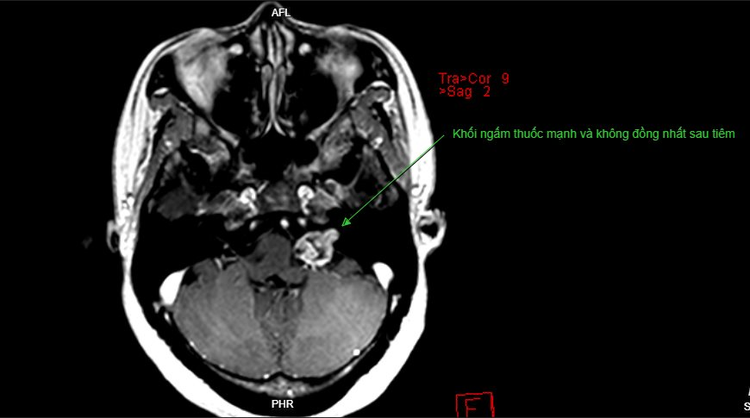

Chụp MRI, bệnh nhân được chẩn đoán u bao dây thần kinh số VIII – u dây thần kinh tiền đình - ốc tai (CN VIII)

Hình ảnh u dây thần kinh tiền đình - ốc tai trên phim chụp của bệnh nhân